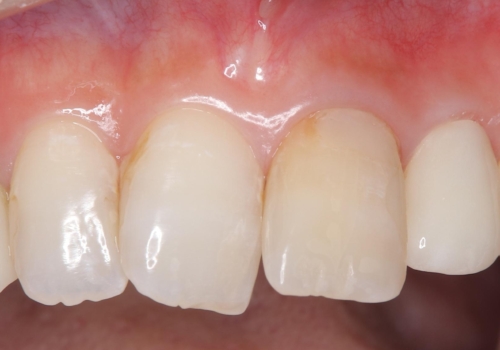

外れ欠けている土台をまずやり替えた後、根管治療後の緊密な封鎖を目的としオールセラミッククラウンをセットしました。